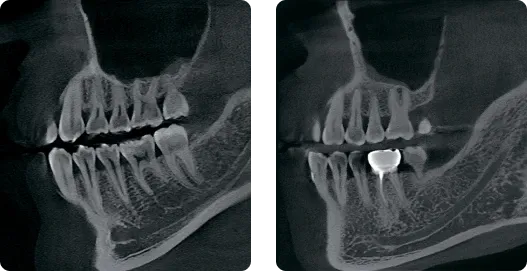

КЛКТ

Когда вам нужно сделать снимок быстреe…

До 4,9 секунды сканирования и 4х секунд 3D-реконструкции!

Когда вам нужно увидеть больше деталей…

До 70 мкм в Endo режиме!

Сверхвысокое разрешение

Когда вам нужна очень точная детализация…

До 70 мкм режим сканирования для эндодонтии.

КТ-изображение с высоким разрешением в определённой области.